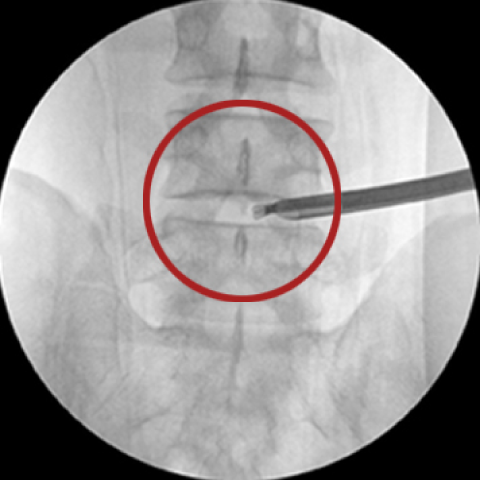

고주파수핵성형술, 플라즈마감압술

직경 2mm 이내의 가느다란 주사바늘을 문제가 생긴 디스크에 삽입하여 고밀도이온화장(플라즈마장)을 쏘아 척추신경을 압박하는 디스크 내의 분자를 분해하고 녹인 후, 수축 응고 시키는 치료법입니다.

고주파 수핵성형술은 전신 디스크가 완전히 파열되지 않거나 아직 나이가 젊고 상태가 수술할 정도로 심각하지 않은 경우 적용됩니다. 문제가 있는 디스크에만 적용하기 때문에 다른 근육과 신경의 손상 위험이 적고 요추관 협착증이나 척추 불안정증이 있는 경우에는 시술하지 못합니다.

□ 이동식 X-ray(C-arm X-ray)로 진행 모습을 실시간으로 확인이 가능해 안전함